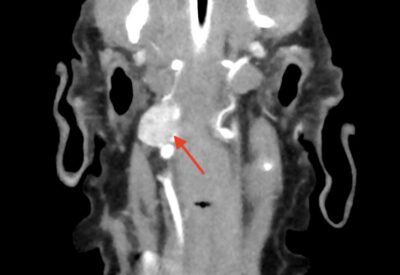

CT検査の結果、腸のしこりとは別に頸にしこりが見つかり、検査の結果、頸動脈小体が疑われました。

この腫瘍は、喉の奥にしこりができるため、気づいた時にはかなり進行しており、手術ができない場合が多いです。

また、この腫瘍は頸の血管から発生するため、進行すると、脳へ広がってしまうこともあります。

このわんちゃんも頸を触っても気づかないくらいの大きさでたまたまCT検査で見つかったので、ご家族と相談の結果、手術を実施することとしました。